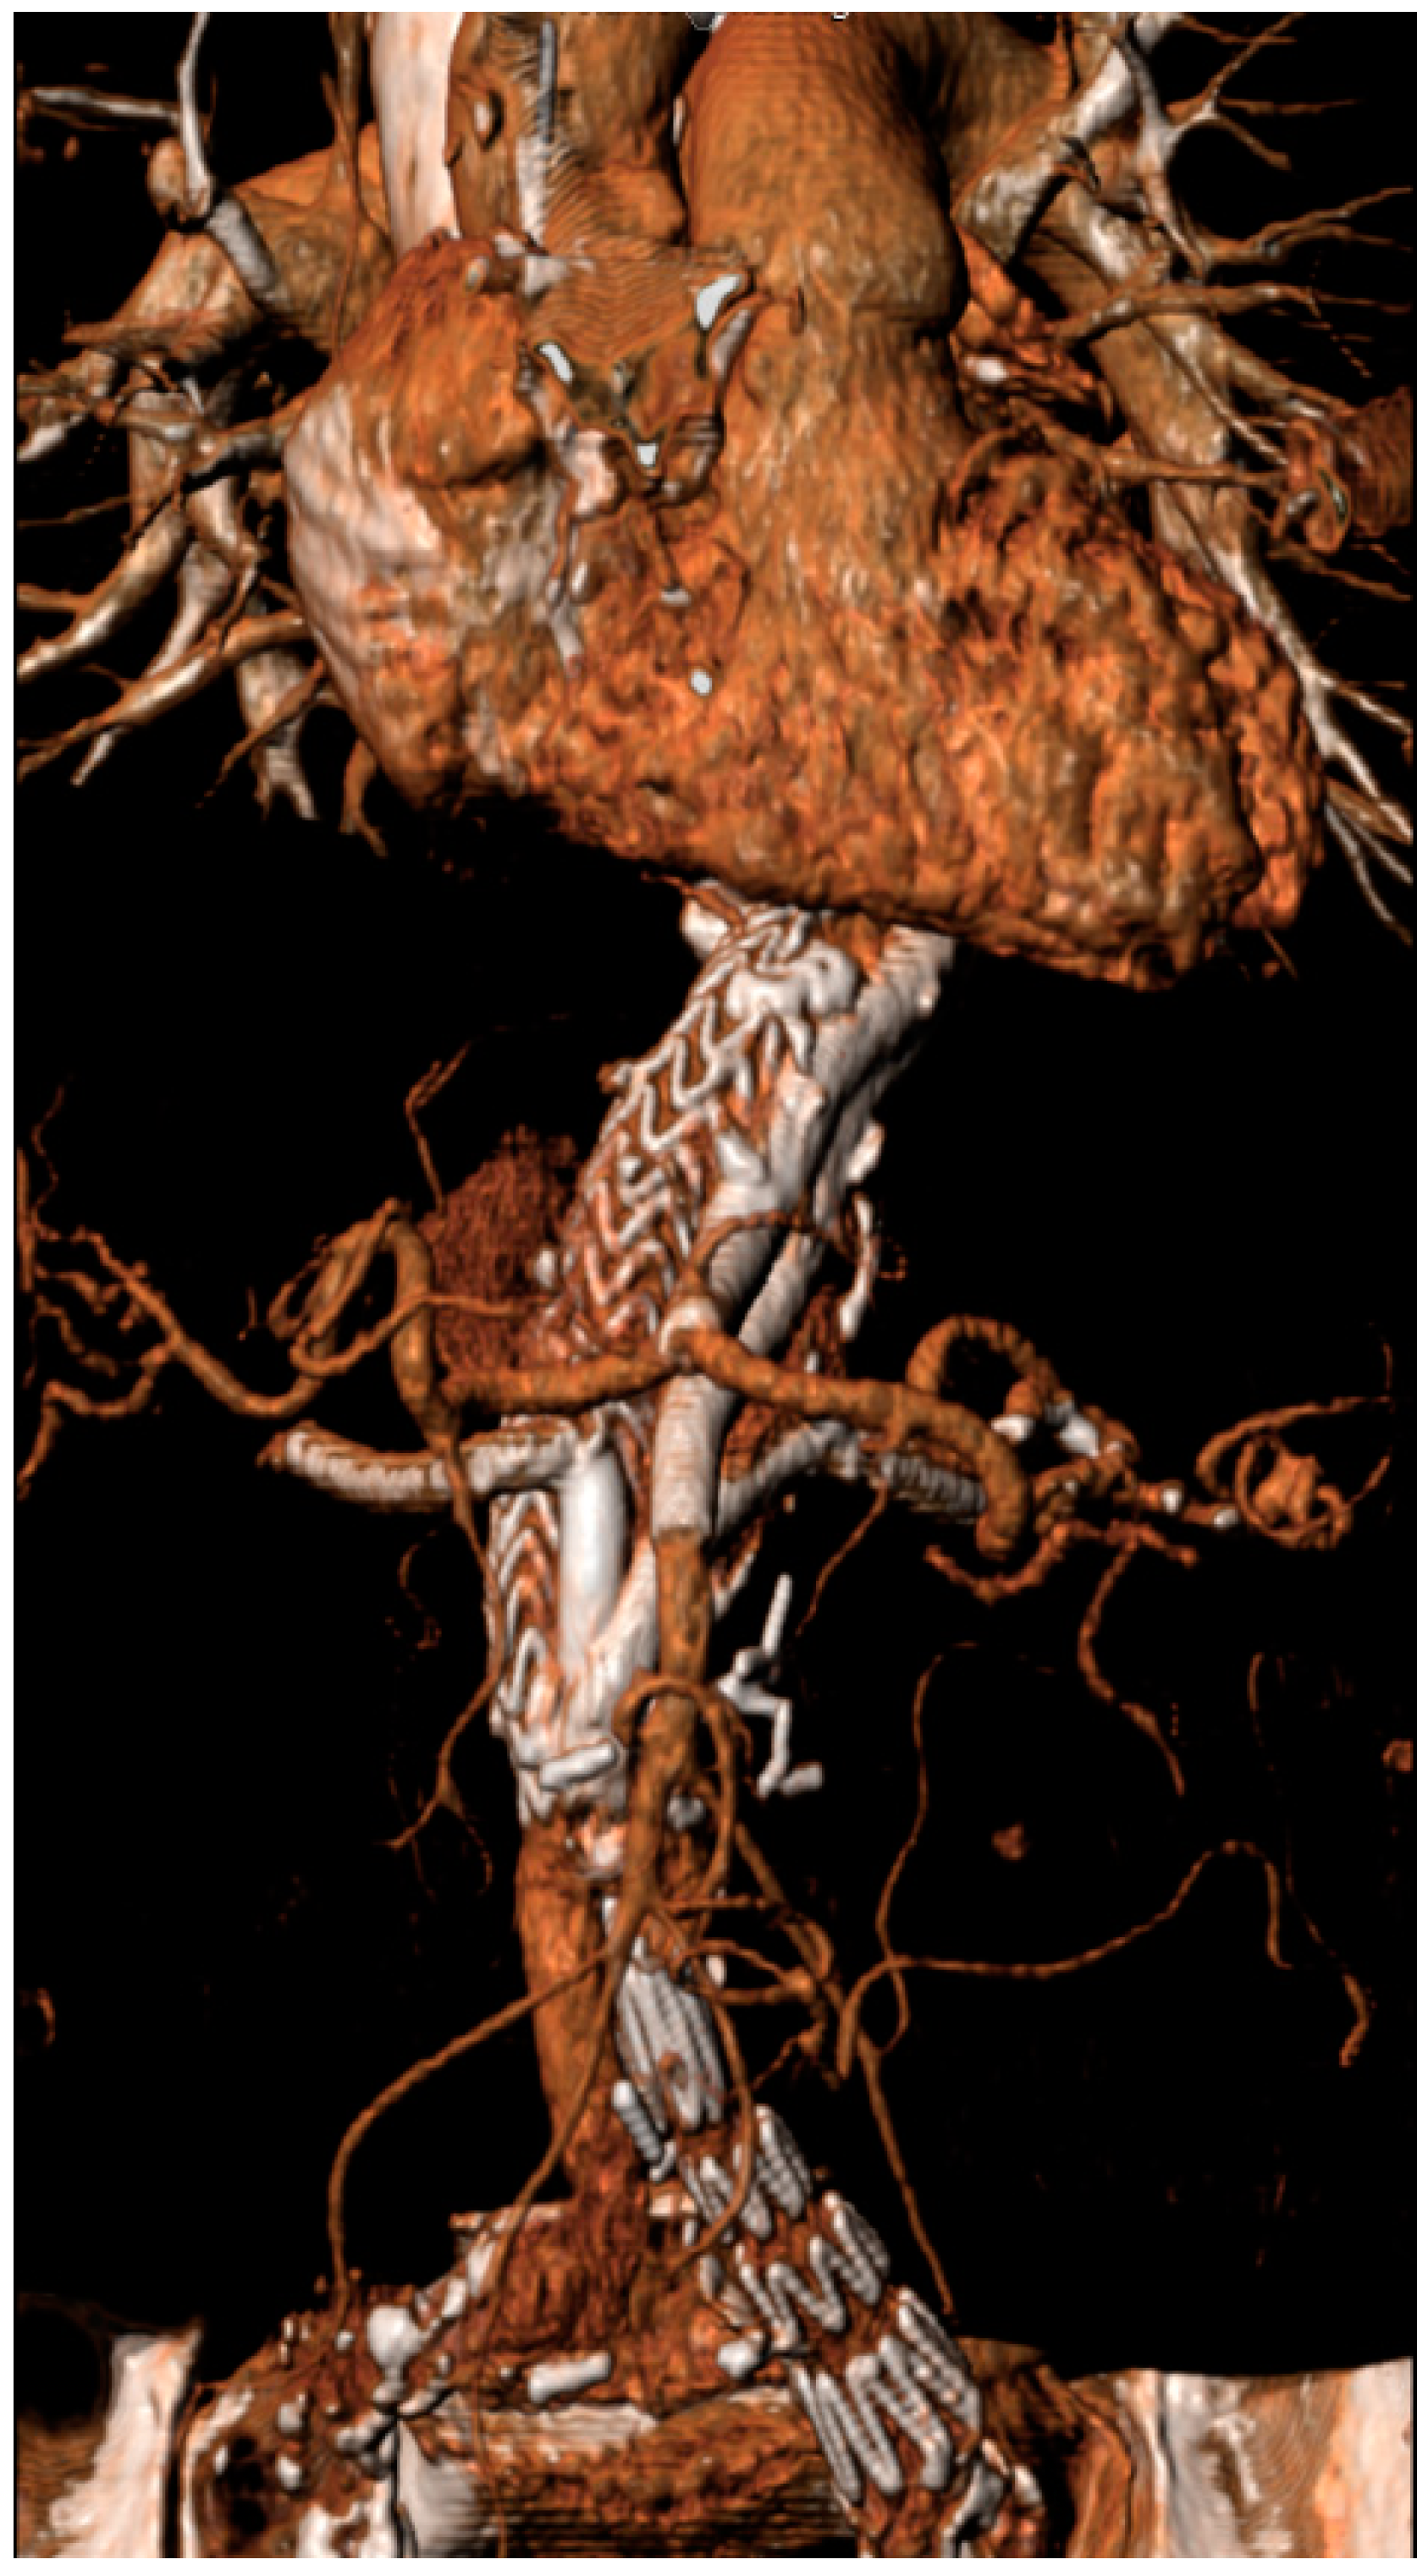

2.3. Endovascular Aortic Repair and Parallel Stent Graft Technique

| Number of parallel grafts | 39 (23 Chimneys, 16 Periscopes) | |